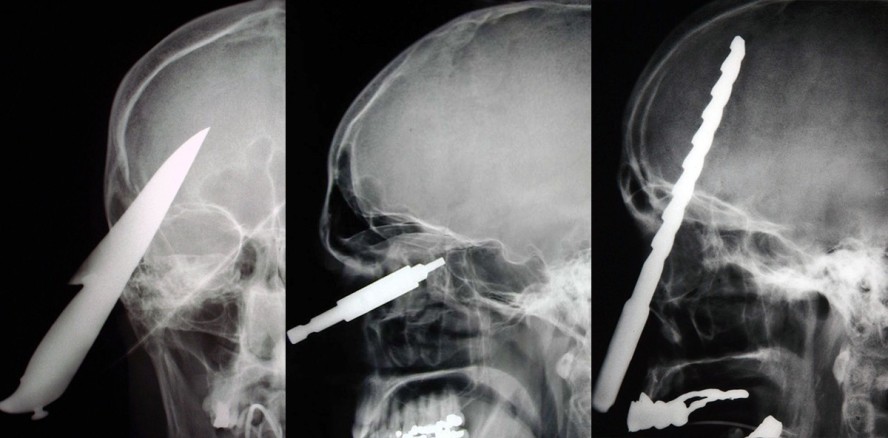

Pfählungsverletzung: Bohrer im Kopf. Ein heute 70-jähriger Mann wurde von einer herabfallenden Bohrmaschine getroffen. Der Metallbohrer dringt tief in den Schädel ein. © Klinik für Mund-, Kiefer- und Gesichtschirurgie, Charité Universitätsmedizin Berlin